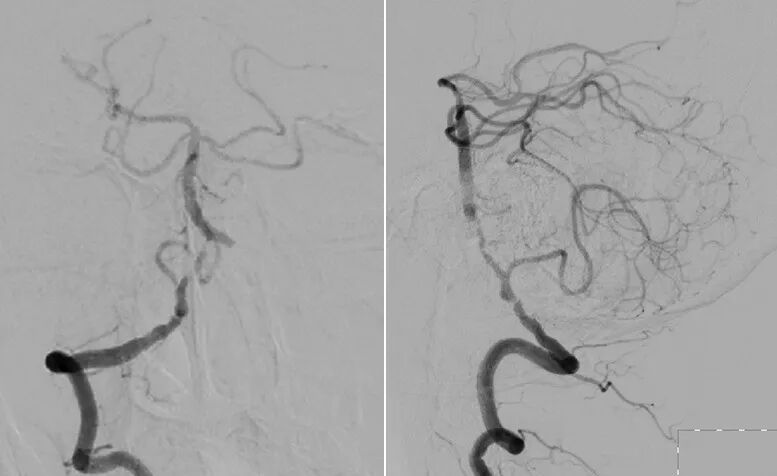

内科治疗后仍有新发梗死(2022.8.8):

导丝怎么扩【载药时代 球扩天下】NOVA DES®颅内药物洗脱支架在椎动脉颅内段重度狭窄的应用二例_https://www.jmylbn.com_新闻资讯_第8张

导丝怎么扩【载药时代 球扩天下】NOVA DES®颅内药物洗脱支架在椎动脉颅内段重度狭窄的应用二例_https://www.jmylbn.com_新闻资讯_第9张

重要影像结论:桥脑新发亚急性梗死灶,右侧椎动脉重度狭窄。